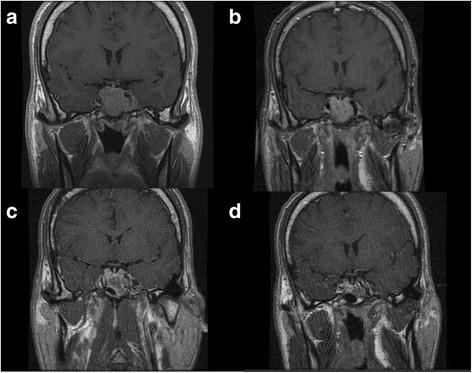

Here we report the case of a 41-year-old acromegalic man with a mixed GH/PRL pituitary adenoma post-surgical resistant to first-generation SRLs both alone and in combination with cabergoline and PEG who achieved biochemical and tumor control with the combined triple treatment with pasireotide, PEG and cabergoline without adverse events and with a good compliance to treatment.

在此,我们报告一例41岁的肢端肥大症男性患者,其患有生长激素/泌乳素混合型垂体腺瘤,术后对第一代SRLs单药治疗以及与卡麦角林和PEG联合治疗均耐药,而采用帕西瑞肽、PEG和卡麦角林三联联合治疗实现了生化指标控制和肿瘤控制,且无不良事件发生,患者对治疗的依从性良好。